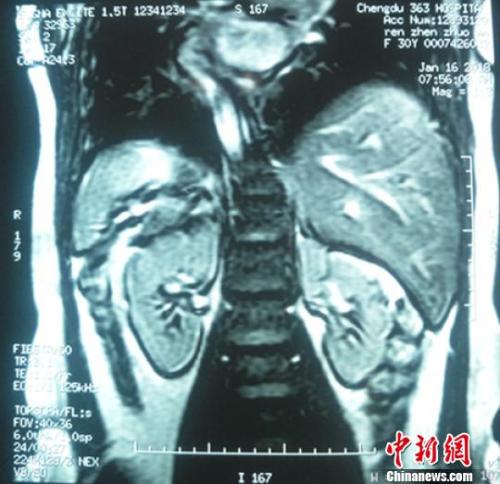

镜面人核磁共振检查画面,内脏位置与常人相反。 王鹏 摄

“正常的胆结石患者均是右下腹疼痛,但她却是左下腹疼痛。”1月15日,该医院胃肠胸外科副主任医师陈浩林发现,前来就诊的王女士胆结石疼痛位置与常人相反,经过多方检查,发现她内脏位置居然与常人相反,是“镜面人”。

据介绍,“镜面人”即心脏、肝脏、脾脏、胆等器官的位置与正常人相反,心脏、脾脏在右边,肝脏位于左边,心、肝、脾的位置好像是正常脏器的镜面像,其发生几率为百万分之一。